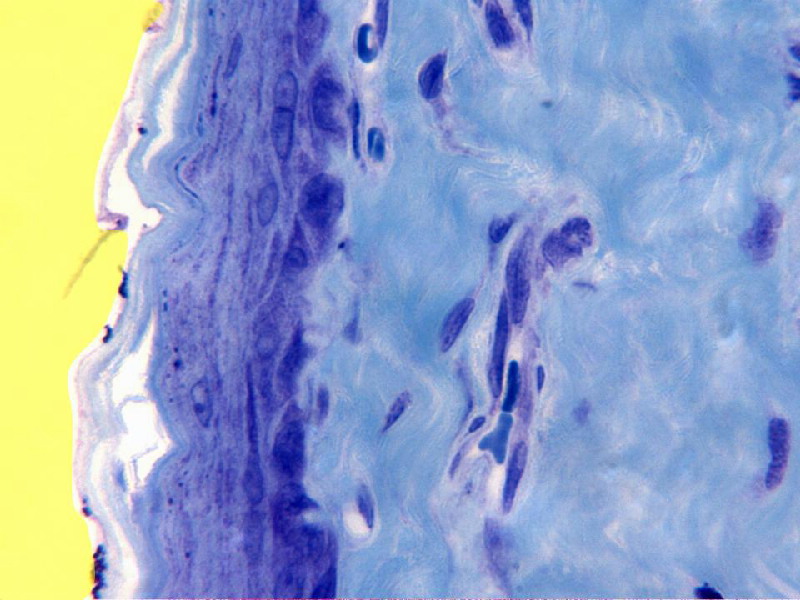

Detalle con el objetivo de 100x

de la parte próxima a la luz

(amarillo) del

órgano. Se observa el

epitelio

plano estratificado con las

células superficiales

descamándose. Nótese la

diferencia entre dichas células,

más planas y las profundas, de

prominente y bien pigmentado

núcleo. En la

submucosa son

visibles abundantes fibras de

colágeno, de trayecto sinuoso y

teñidas de azul. El resto lo

ocupan numerosos

núcleos, fundamentalmente de fibrocitos

y algunos

vasos sanguíneos